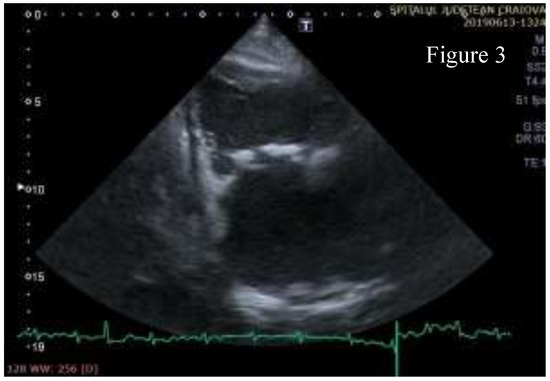

Figure 3.

Right ventricular inflow view- the anterior and posterior cusps of the tricuspid valve have massive calcifications.